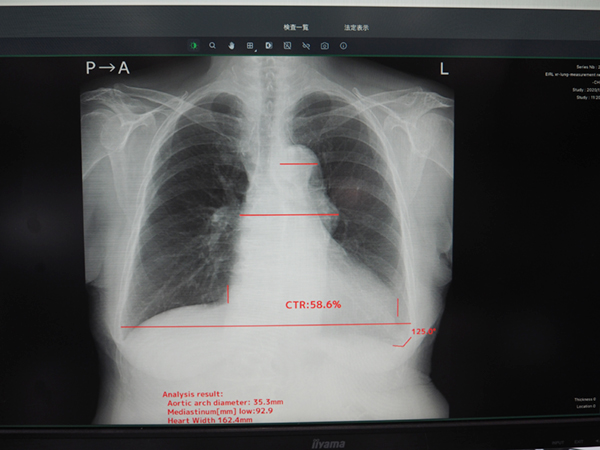

胸部X線画像から異常陰影の候補点を検出する「EIRL Chest Screening」は,4所見(結節影,浸潤影,間質性陰影,無気肺)または肺結節のみを検出することができ,加えて5つの計測(胸腔内の空気含有面積,心胸郭比,縦隔比,大動脈弓の径,肋骨横隔膜角)と過去画像との比較が自動で行われる。日本放射線技術学会が公開しているデータセットを基にした検証では,肺結節の検出精度は,検出が困難な肺結節影(読影難易度1〜5の3)でも感度90.0%の結果を示している。また,自動計測により複数の医師が計測する場合にも計測誤差を抑制できる。過去比較では,経時的変化を画像上に表示する機能を有し,変化の内容(増大や減少)によって□や〇で表示され,一目で把握しやすい。

「EIRL Chest Screening」異常陰影候補の検出結果表示

自動計測により医師間の計測誤差を抑制できる。